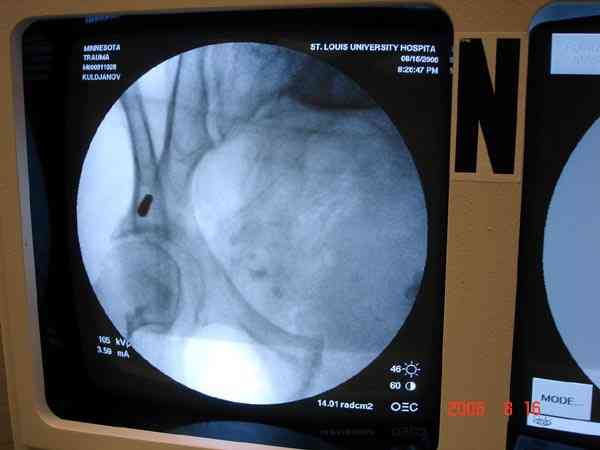

Примерно такой фиксатор наложил вчера ночью, но патология была экстренная травма: больному 53 года, поступил после мотоциклетной травмы, черепно-мозговой, абдоминальной, челюстно лицевой с потерей одного глаза, сосудистой и из скелета перелом крестца слева с диастазом симфиза и множественные переломы ребер.

Для стабилизации перелома и кровопотери, сперва была попытка наложения простыни вокруг таза для уменшения объема таза. Для оперативного доступа в области живота и передней части таза простыню заменили на Beam Bag (матрац который после удалении воздуха принимает контуры тела).

Одновременно с хирургами, которые занялись ксплоративной лапаротомией, мы приступили к фиксации временным аппаратом для уменьшения диастаза симфиза. После установки аппарата удалось стабилизировать давление, потом наше место занял сосудистый хирург, который нашел кровоточащую левую артерию epigastrica. Кровоточаший сосуд затромбизировал эндоваскулярно введением 4 coil placement.

Много кровепотери было из лицевых ран. Кроме забрюшинной гематомы, крови накопилось в абдоминальной части между мышечными стенками и под кожей. Кровопотерю заместили более 20 доз препаратов крови и INR опустился изначалнего 9.5 до 1.0 в конце. Находится в реанимации, стабильный, надеемся через несколько дней займемся окончательной фиксацией переломов костей таза.